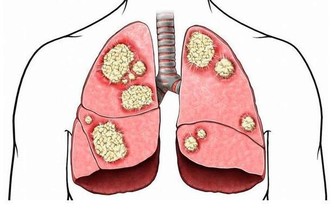

經常憋尿不僅容易引起膀胱損傷,還易造成細菌繁殖,嚴重的話,可能造成尿路感染,引發腎炎甚至尿毒症。

***4. 亂用藥***

據統計,急性腎衰竭的案例中,大約有四分之一是藥物引起的。

不只處方藥,不少非處方藥也有一定的毒性,最常見的是人們感冒後自行服用的抗生素、解熱鎮痛藥、部分中成藥等。

總之,一定要遵照醫囑用藥。